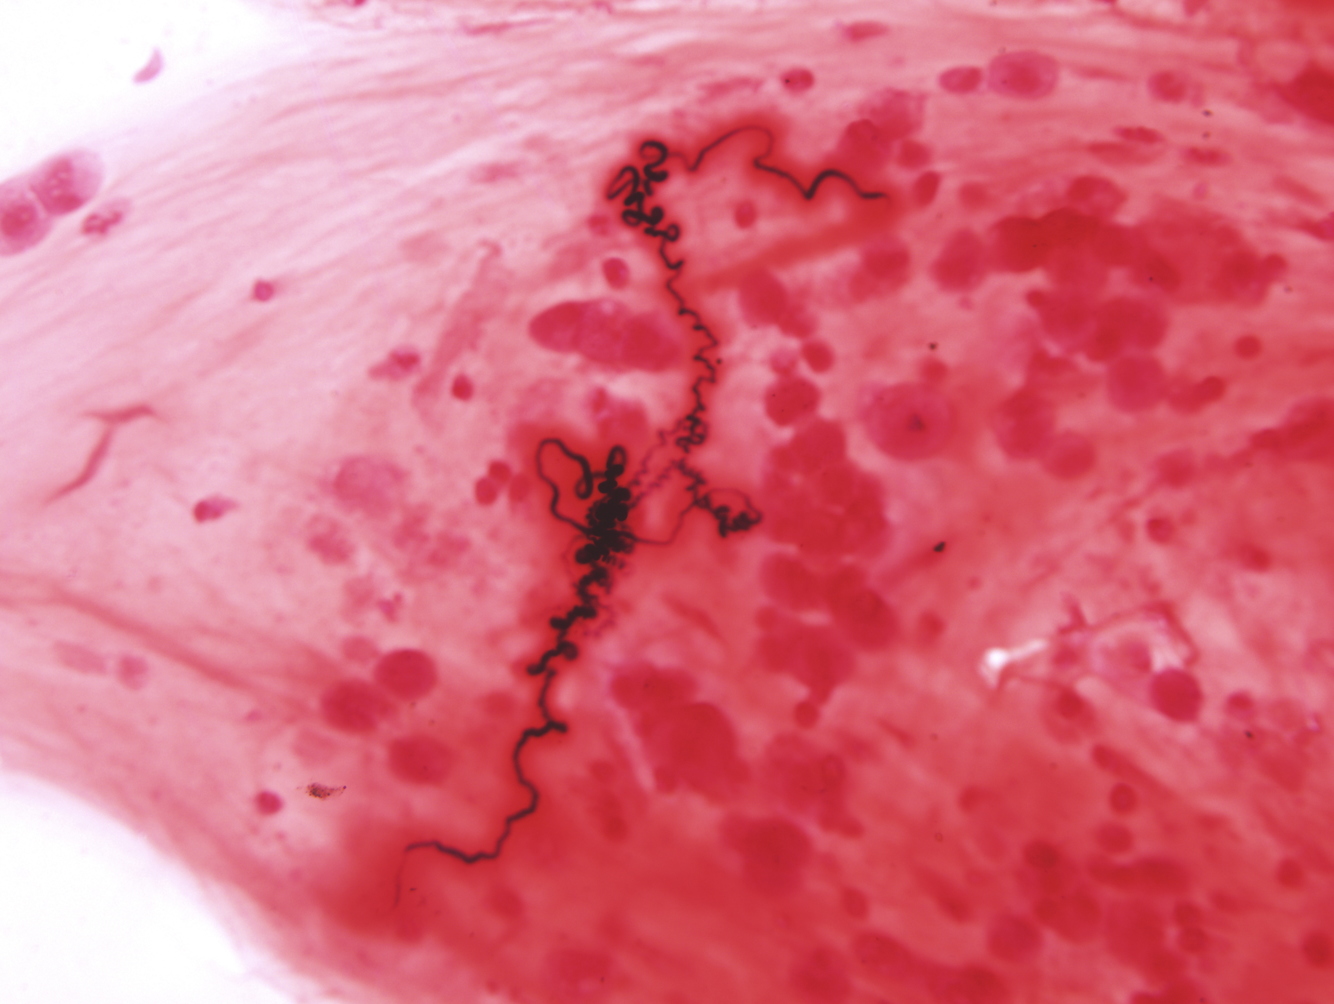

Describe 2 histologic findings in asthma

(1) Curschmann spirals (shed epithelium forms wholed mucus plug)

(2) Charcot-Leyden crystal (eosinophil-dervied needle-like crystals) - see next slide for image

Charcot-Leyden crystals

eosinophil-dervied needle-like crystals